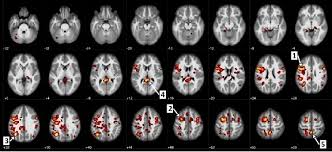

Brain Regions Activated More In 10 Schizophrenic Patients Without Download Scientific Diagram

Brain Regions Activated More In 10 Schizophrenic Patients Without Download Scientific Diagram from www.researchgate.net

Pdf | schizophrenic patients suffer from hallucination which its causality is not yet fully understood. Articles on schizophrenia and your brain. Michael green, neuroscientist and professor of psychiatry and biobehavioral sciences at ucla, has been fascinated with the human brain. Brains with schizophrenia also show neurochemical differences when compared with normal brains. • brain protection in schizophrenia, mood and cognitive disorders.

Pdf | schizophrenic patients suffer from hallucination which its causality is not yet fully understood schizophrenia. Major symptoms include hallucinations (typically hearing voices), delusions.